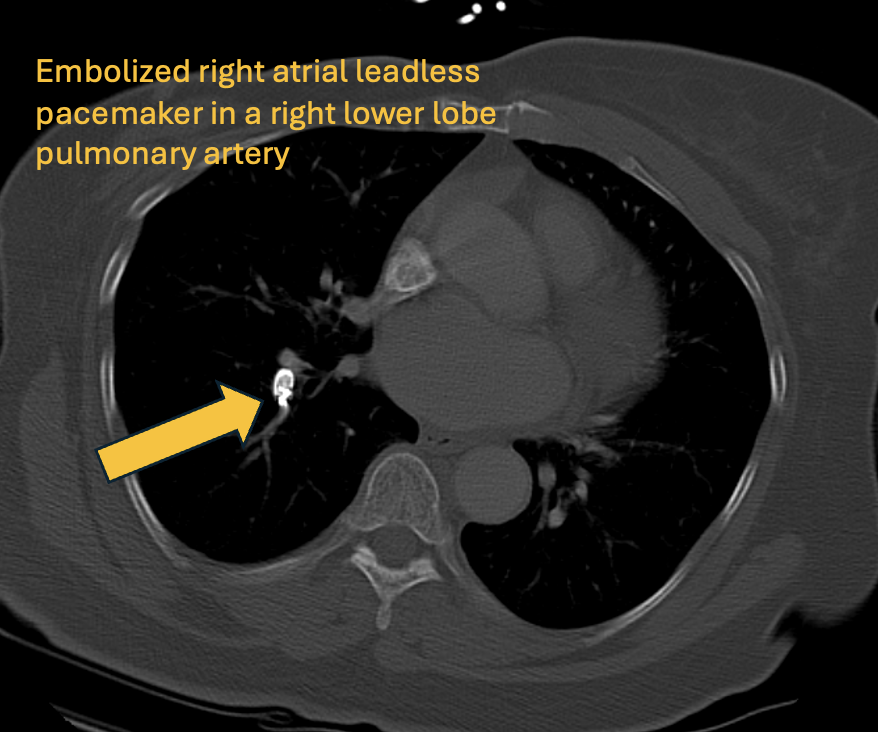

🫀Answer: Embolized right atrial leadless pacemaker! 🦓Uncommon complication, usually peri-procedural 🚧More common in patients with high BMI, tricuspid regurgitation, and atrial dilation 🥅Next step is retrieval of device with snare ❓Would you have caught this on first pass?

0

1

6

🚨Challenging case alert! 👩‍🦳72yo woman presents with acute dyspnea following dual-chamber leadless pacemaker placement. ➡️What is the device shown and is it in the correct location? #Radiology #Cardiology #Medtwitter #Radres

7